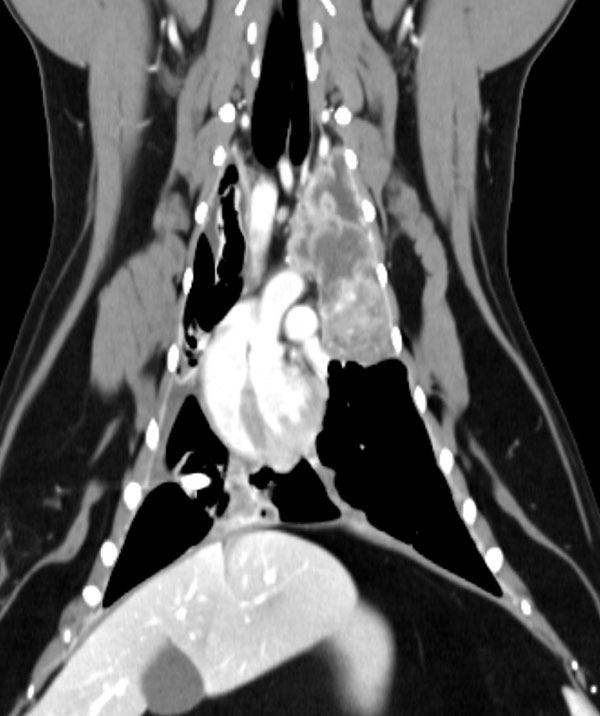

종양외과(Oncologic Surgery)는 종양 또는 암이 발생한 부위의 외과적 치료를 담당하는 분야입니다. 고양이를 포함한 동물들의 종양은 악성일 수도 있고, 양성일 수도 있으며, 외과적 제거나 치료적 수술을 통해 종양을 처리합니다. 종양외과는 종양의 크기, 위치, 악성 정도 등에 따라 맞춤형 수술적 방법을 선택하여 치료합니다.